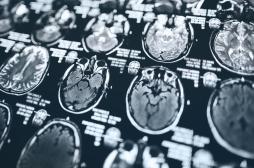

LES MALADIES

SYMPTÔMES